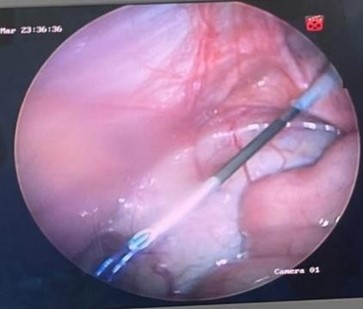

Figura 3. Introducción de aguja epidural con hilo prolene 2.0, en forma de lazada, de manera percutánea, en región inguinal derecha

Figura 4. Bordeo de anillo